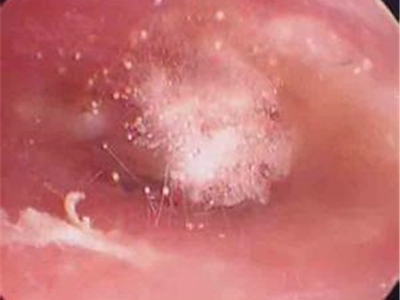

外耳道

脱屑

外耳道炎外耳道有细小的白色脱屑图

外耳道炎患者检查时可见外耳道有很多细小的脱屑,表面呈白色,同时周围皮肤发红,并伴有轻微肿胀,患者自觉耳部疼痛、瘙痒等症状。